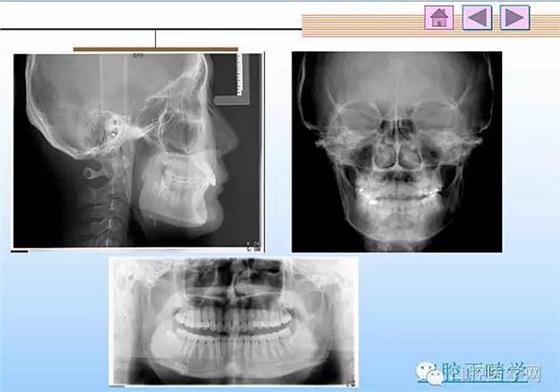

口腔正畸學(xué)病歷書寫:歷來臨床的病歷書寫都是一個(gè)普遍而又實(shí)際困難的地方,尤其是口腔正畸學(xué),很難有規(guī)范的書寫格式,在這里,把我精心保存的病歷書寫用幻燈的格式傳給大家,便于觀看,從教學(xué)到臨床都有很好的指導(dǎo)作用。